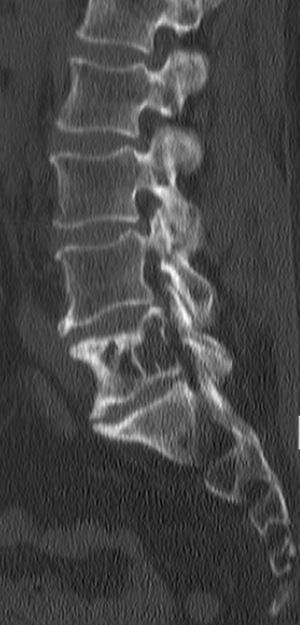

Plasmozytome bestehen aus maligne entarteten Plasmazellen. Bei mehreren Herden spricht man vom multiplem Myelom. Die Mehrzahl der Herde sind osteolytische Knochenherde.

Knochenmark, osteolytische Herde, selten extramedullär oder Plasmazellleukämie.

B: Bone lesions, Knochenläsionen